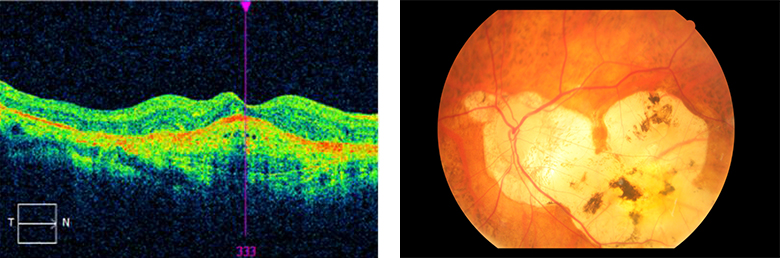

• 비삼출성 황반변성